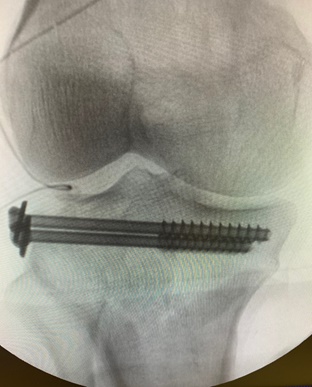

Σε επιτυχημένη αρθροσκοπική χειρουργική επέμβαση αποκατάστασης κατάγματ...

Σε επιτυχημένη αρθροσκοπική χειρουργική επέμβαση αποκατάστασης κατάγματ...